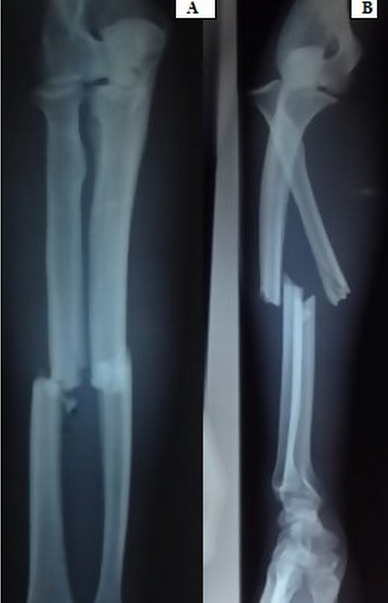

La fracture luxation de Monteggia de type IV, selon la classification de Bado, est une lésion rare. Elle est définit par la présence d'une fracture des deux os de l'avant bras avec une luxation antérieure de la tête radiale. Son traitement est très exigeant en matière de réduction et de restauration de la longueur des deux os du cadre antébrachiale condition sans laquelle la réduction de la luxation de la tête radiale devient impossible ce qui va compromettre la fonction de la prono-suppination de l'avant-bras. Nous rapportons le cas d'un homme de 32 ans qui s'est présenté aux urgences chirurgicales pour une fracture de Monteggia correspondant au type IV selon la classification de Bado. Un traitement chirurgical par deux plaques type DCP (dynamic compression plate) a permis d'obtenir une réduction de la tête radiale automatiquement après le rétablissement de la longueur des deux os du cadre antébrachial. Une immobilisation par une attelle brachio-antébrachio-palmaire a été réalisée pendant trois semaines suivies d'une rééducation.